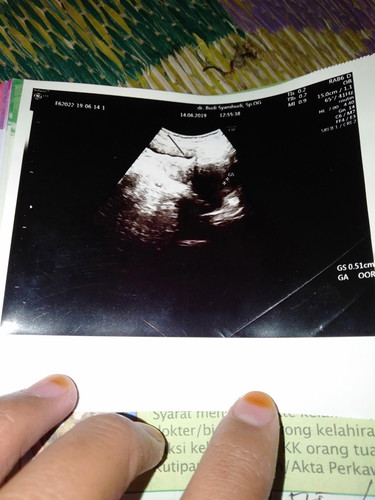

usg

Bun ini aku usg pertama kali waktu hmil 4 minggu baby nya msh kecil banget kata dokter msh pembesaran dan pembentukan ada yg sama gk bun ? Nnti usg lgi kpan ya bun biar bisa liat baby nya ?

Dlu sy pertama kali usg abdomen jg di usia 4w. Emang msh kecil bgt kantongnya. Biasanya dokter menganjurkan utk balik kontrol 2 minggu kemudian / uk 6w bun. Dokternya gak bilang kah? Tp kebanyakan org usg di usia 6w jg msh kelihatan kantongnya aja klo pake usg biasa. Tp klo pake usg transvaginal janin udh kelihatan meskipun kecil bgt berikut denyutnya sudah ada. Tp biasanya usia segitu dokter gak kasih dengar denyutnya. Klo mau pake usg biasa mgkn di usia 7-9 w udh bs diliat janinnya..

Iya Bun 4minggu biasanya baru kantung aja. Kalau kemarin pas di periksa ga ada kendala apa2, periksa lagi sebulan kemudian Bun. Kalau ada kendala, baru 2minggu kemudian baliknya.

ak 4w malah masih penebalan rahim, trus suruh balik lagi 2w tp ak gk balik smpai 10w, pas usg 10w uda keliatan jelas baby & djj,